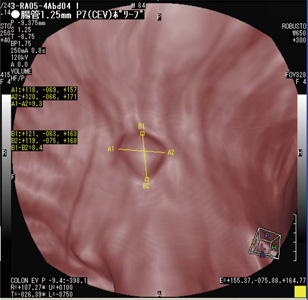

また,大腸領域の経路については,MPR像上で経路算出開始点と算出方向を設定するだけで算出され,結果は3D画像上に表示される(図1右下)。

図3に示す3D-MPR表示モードは,大腸管腔外組織を観察する場合に適している1)。この表示モードでは大腸内部のみが3D画像であり,その周囲はMPR像である。この融合画像によって,ポリープなどの突起物の内部構造観察と,仮想内視鏡画像である3D画像の同時観察が行える。仮想内視鏡画像と3D-MPR像は,図1の右下の位置に表示され,どの位置で大腸内部を観察しているかは,3つのMPR画面によってガイドされる。

図1 CT Colonoscopy